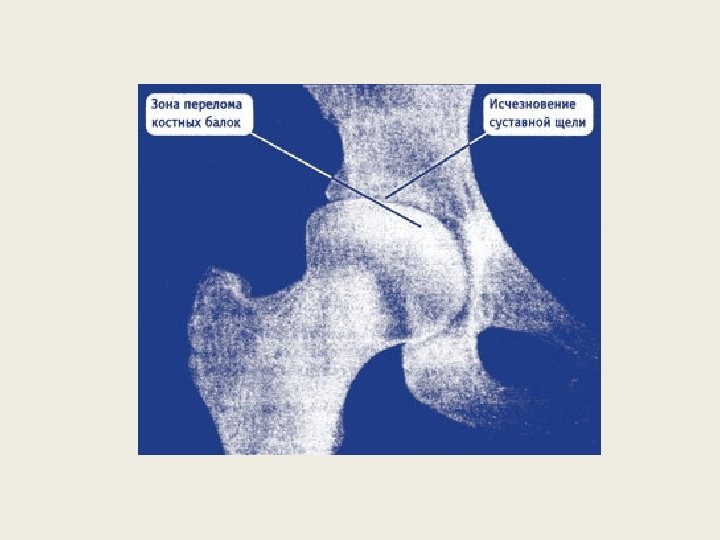

Развивается артроз тазобедренных суставов (коксартроз) обычно после сорока лет. Женщины болеют чуть чаще, чем мужчины. Коксартроз может поражать как один, так и оба тазобедренных сустава. Но даже в случае двустороннего поражения сначала, как правило, заболевает один сустав, и лишь потом к нему «подтягивается» второй. Основной симптом коксартроза — боль в паху. Чаще всего боль из паха распространяется вниз по ноге по передней и боковой поверхности бедра. Иногда такие болевые ощущения распространяются еще и на ягодицу. Обычно боль, идущая от паха по передней и боковой поверхности бедра, доходит вниз только до середины бедра или до колена. Ниже колена эта боль почти никогда не идет. Лишь очень редко боль доходит до середины голени, но не опускается до пальцев ног — в этом отличие коксартрозной боли от боли, вызванной повреждением поясницы (например, грыжей межпозвонкового диска). Боли возникают в основном при ходьбе и при попытке встать со стула или с кровати. Часто именно самые первые несколько шагов после вставания бывают особенно болезненными. Потом, когда болеющий человек расходится, ему может стать чуточку полегче. Но после долгой ходьбы болевые ощущения вновь

На ранних стадиях коксартроза болевые ощущения в паху и бедре выражены слабо, чаще отмечается лишь легкое прихрамывание и несильная ноющая боль при ходьбе. Поэтому заболевший человек не спешит к врачу, надеясь на то, что проблема каким то образом разрешится сама собой. Однако идет время, болезнь прогрессирует, и боле вые ощущения нарастают. В большинстве случаев это происходит постепенно, но иногда, после неудачного движения или нагрузки, могут происходить довольно резкие обострения, которые длятся от нескольких дней до нескольких месяцев. Постепенно к болевым ощущениям добавляется ограничение подвижности больной ноги. Заболевшему человеку трудно отвести ногу в сторону, подтянуть ногу к груди; трудно надеть носки или обувь. Заболевший человек вряд ли сможет сесть на стул «верхом» , широко раздвинув ноги — или сделает это с большим трудом. По мере прогрессирования коксартроза у может появиться все более отчетливый хруст в больном суставе при движении и ходьбе. Обычно он бывает связан с трением суставных поверхностей, не идеально подогнанных друг к другу по форме. Конечно, у некоторых людей суставы могут и без коксартроза пощелкивать, и весьма громко. Но артрозный хруст имеет совсем другую тональность, он грубый и «сухой» . И если на первой стадии

Коксартроз (остеоартрит тазобедренного сустава). • 1). Выявлять как можно раньше. • 2). Делать ВСЕ возможное для стабилизации процесса (остановить прогрессирование болезни): БАД, ЛФК, … • 3). Если нужна операция – продумайте подготовку и поддержку организма БАДами. • 4). И «пока без» операции, и «перед» ней, и «после» нее, оптимально – «ВМЕСТО» операции (как профилактическая поддержка ЗДОРОВЫМ суставам) – БАДы Вам пригодятся всегда.